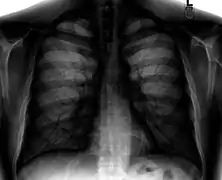

Different views (also known as projections) of the chest can be obtained by changing the relative orientation of the body and the direction of the x-ray beam. The most common views are posteroanterior, anteroposterior, and lateral. In a posteroanterior (PA) view, the x-ray source is positioned so that the x-ray beam enters through the posterior (back) aspect of the chest and exits out of the anterior (front) aspect, where the beam is detected. To obtain this view, the patient stands facing a flat surface behind which is an x-ray detector. A radiation source is positioned behind the patient at a standard distance (most often 6 feet, 1,8m), and the x-ray beam is fired toward the patient.

Lateral views of the chest are obtained in a similar fashion as the posteroanterior views, except in the lateral view, the patient stands with both arms raised and the left side of the chest pressed against a flat surface.